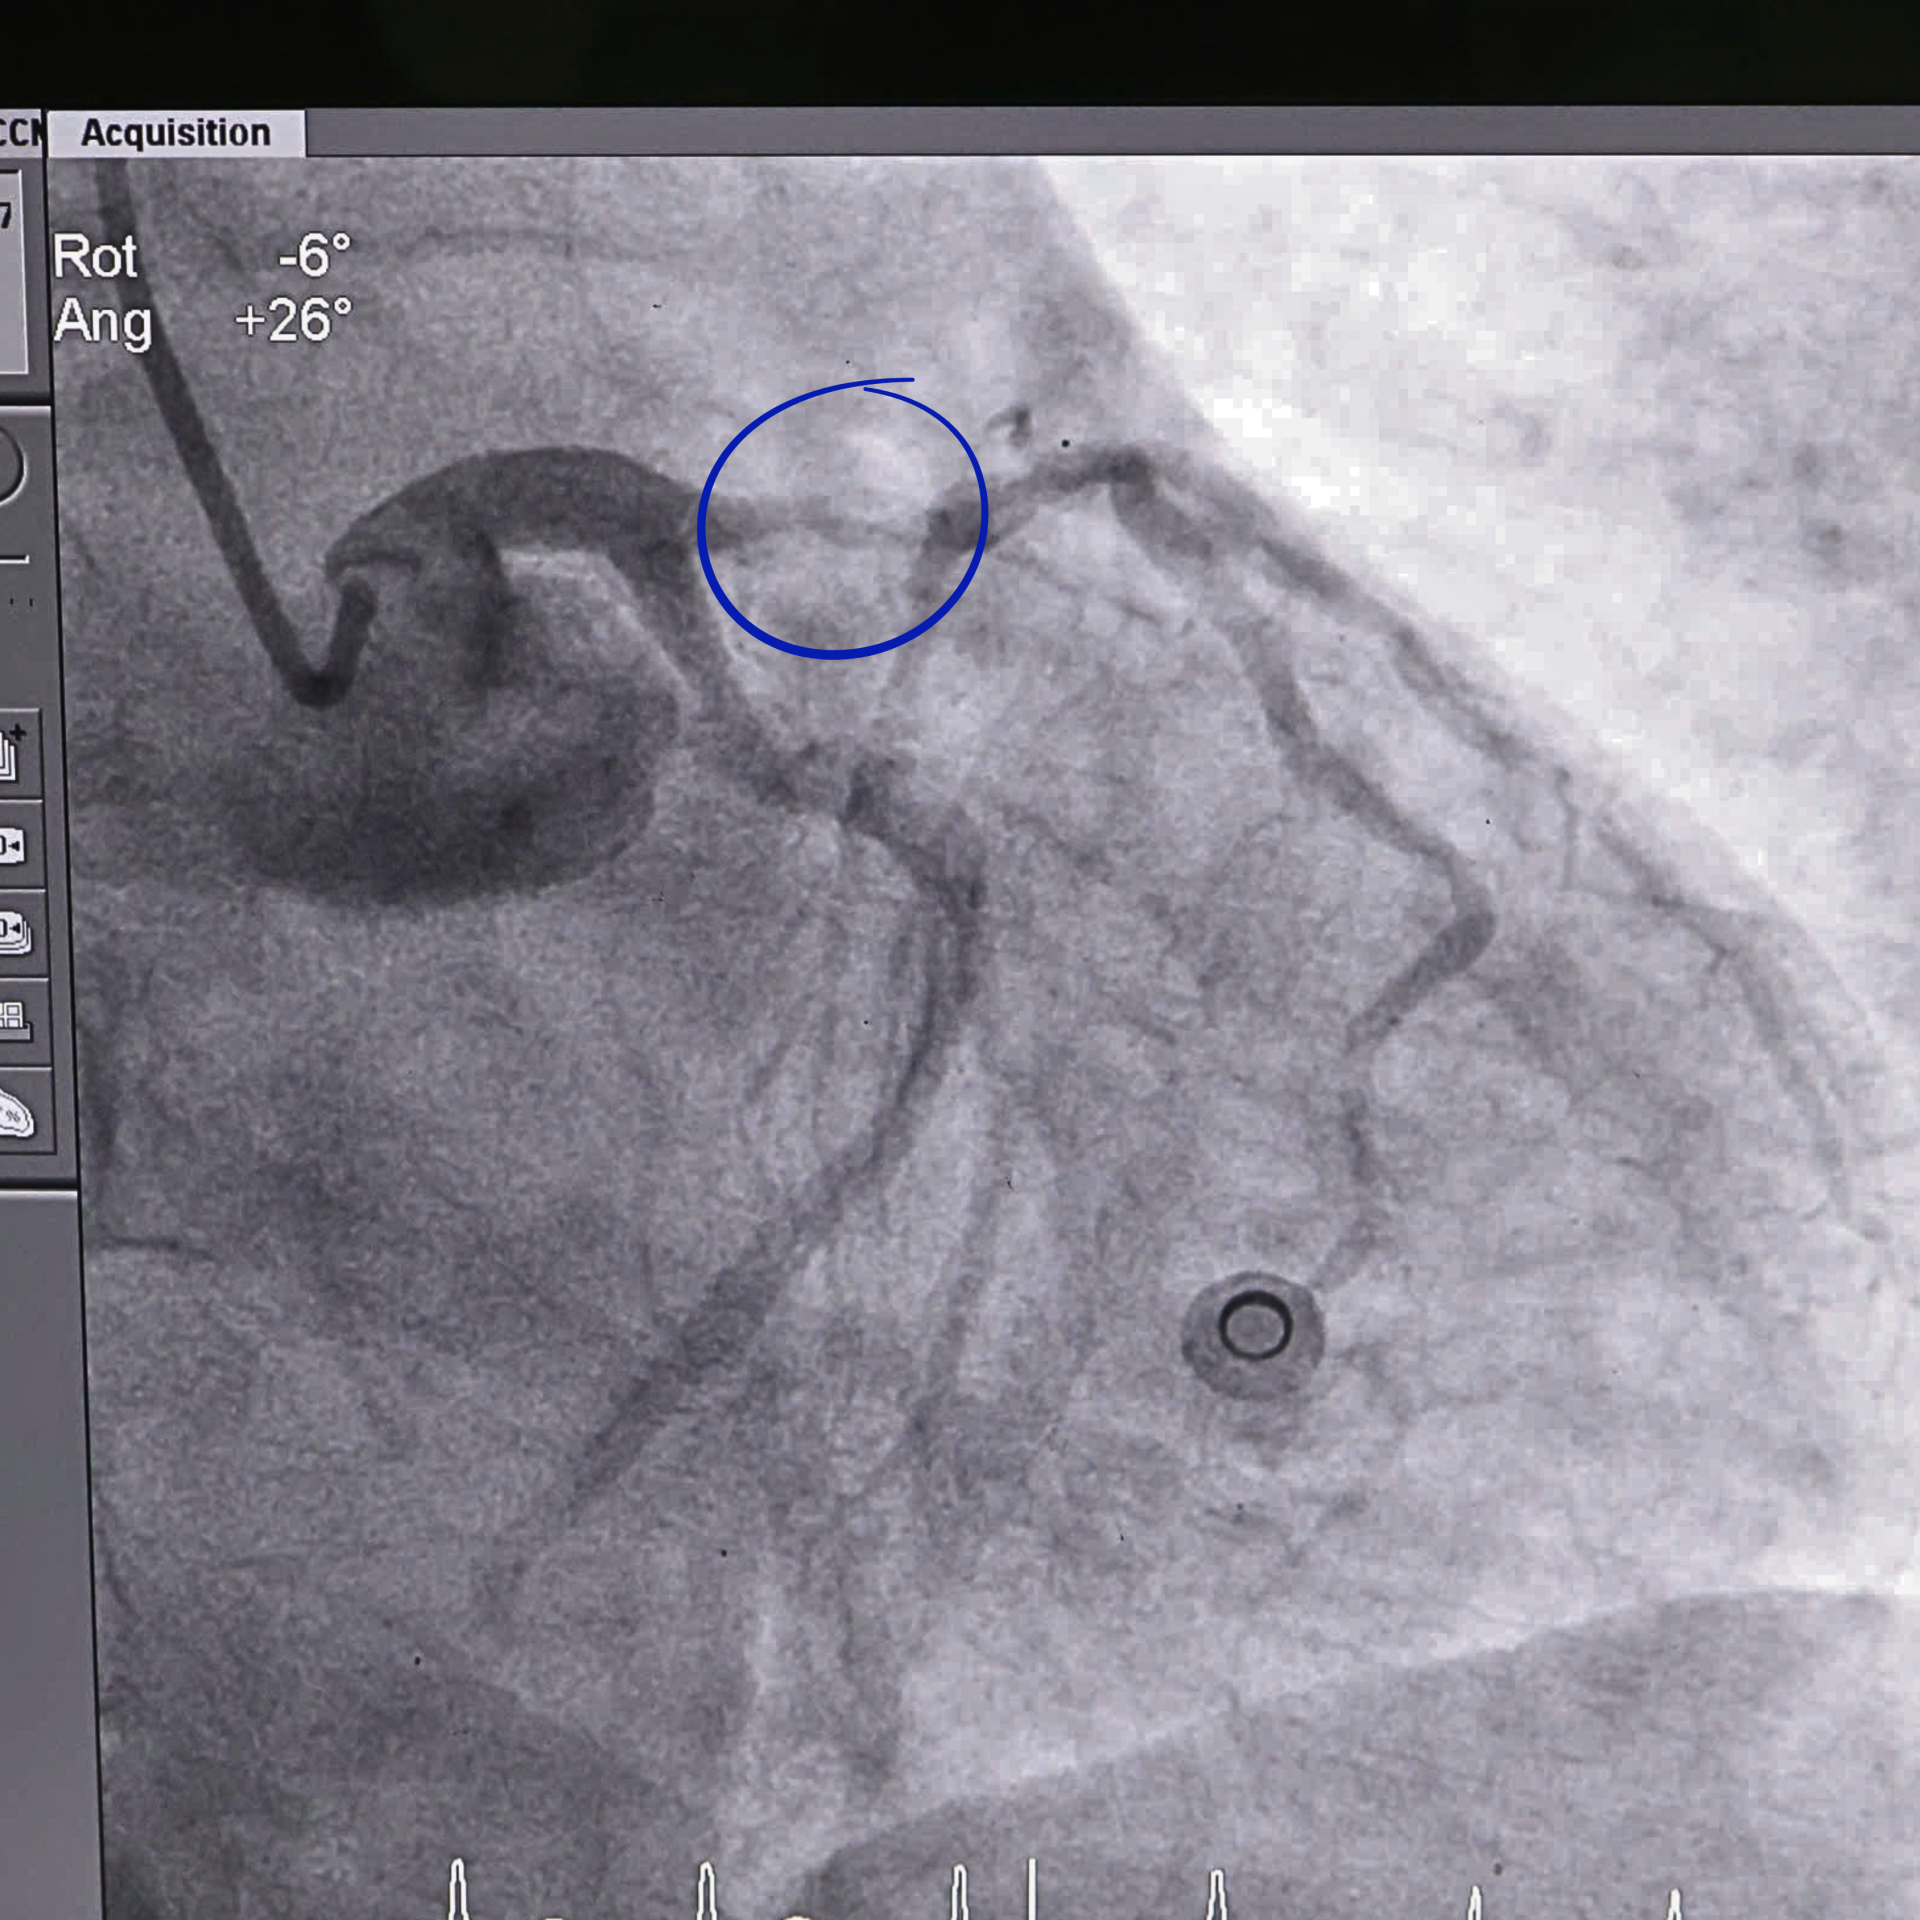

Hình ảnh mạch máu điểm bị tắc của bệnh nhân trước can thiệp.